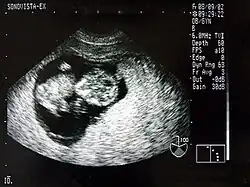

Sonografie einer Schwangeren im Rahmen der Pränataldiagnostik

Ein wesentlicher Vorteil der Sonografie gegenüber dem in der Medizin ebenfalls häufig verwendeten Röntgen liegt in der Unschädlichkeit der eingesetzten Schallwellen. Auch sensible Gewebe wie bei Ungeborenen werden nicht beschädigt, die Untersuchung verläuft schmerzfrei.

Neben der Herztonwehenschreibung (Kardiotokografie) ist sie ein Standardverfahren in der Schwangerschaftsvorsorge. Eine spezielle Untersuchung der Pränataldiagnostik zur Erkennung von Entwicklungsstörungen und körperlichen Besonderheiten ist der Feinultraschall.

2D-Sonogramm eines neun Wochen alten Menschenfötus

B-Mode (B für englisch brightness modulation) ist eine andere Darstellung der Information des Amplituden-Modus, bei der die Echointensität in eine Helligkeit umgesetzt wird. Durch mechanisches Bewegen der Sonde überstreicht der Messstrahl eine Fläche in einer Ebene ungefähr senkrecht zur Körperoberfläche. Der Grauwert eines Bildpunktes auf dem Bildschirm ist ein Maß für die Amplitude eines Echos an dieser Stelle.